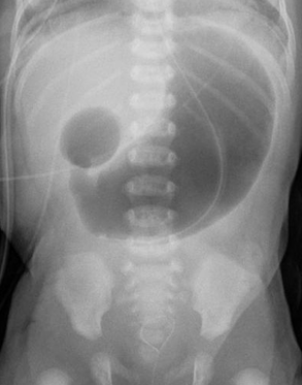

How is duodenal atresia diagnosed?

Abdominal x-ray showing double bubble sign, contrast studies may confirm the diagnosis

Q

Abdominal x-ray showing air-fluid levels